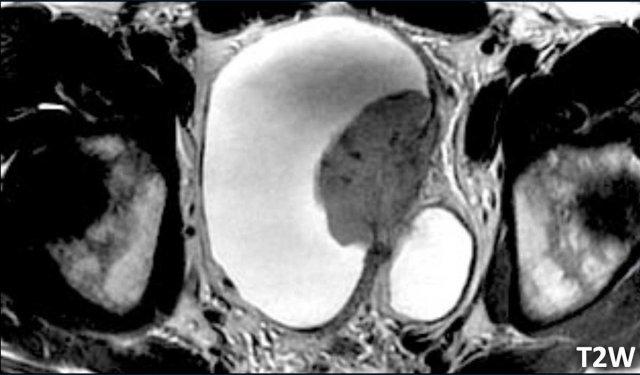

Hình ảnh

Có một khối u nhú lớn ở thành bàng quang bên trái xâm lấn vào đường giảm tín hiệu của cơ thành bàng quang.

Đây là trường hợp khó đánh giá vì có vẻ như có xâm lấn mỡ.

Tuy nhiên, hình ảnh T2W thường đánh giá quá mức xâm lấn mỡ do hiệu ứng thể tích từng phần.

Bước tiếp theo là đánh giá các hình ảnh DCE và khuếch tán để phân biệt giữa VI-RADS 4 và 5.

Các hình ảnh DCE và DWI sẽ giúp phân biệt giữa VI-RADS 4 và 5.

Tiếp tục xem các hình ảnh DCE và DWI…

Quan sát các hình ảnh.

Bạn nhận thấy những dấu hiệu gì?

Dấu hiệu

- DCE: Ngấm thuốc sớm của lớp cơ được thấy rõ ràng trên chuỗi xung DCE.

Bản thân khối u nghèo mạch máu và không lan qua lớp cơ đang ngấm thuốc. - DWI/ADC: Có sự gián đoạn của cơ thành bàng quang, nhưng không có xâm lấn mỡ.

Kết luận

T2W 4/5, DCE 4 và DWI/ADC 4

Điểm VI-RADS cuối cùng: 4